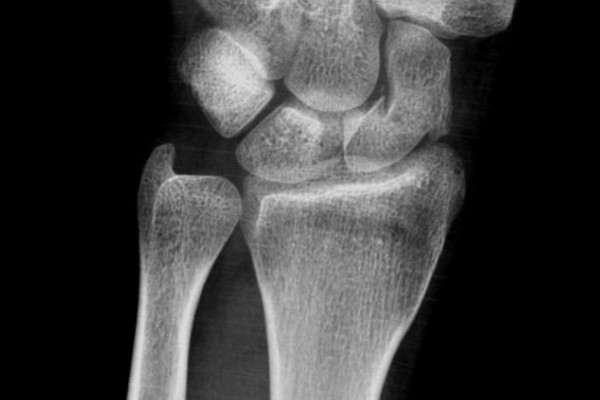

La fractura del escafoides de la muñeca

El diagnóstico de fractura del escafoides en la fase aguda sigue siendo un reto en la actualidad, para llegar a él es imprescindible una alta sospecha clínica y la práctica de una minuciosa exploración de la muñeca junto con un estudio radiológico correcto. Incluso así, a veces es casi imposible objetivar la lesión. Por esto, ante una lesión traumática de la muñeca, producida habitualmente en hiperextensión de la mano, y con una elevada sospecha clínica de fractura del escafoides, aunque no se haya podido confirmar la fractura, se recomienda tratar esta lesión como una fractura del escafoides, y repetir la exploración física i el estudio radiológico entre los 12-15 días después del traumatismo para confirmar o descartar el diagnóstico.